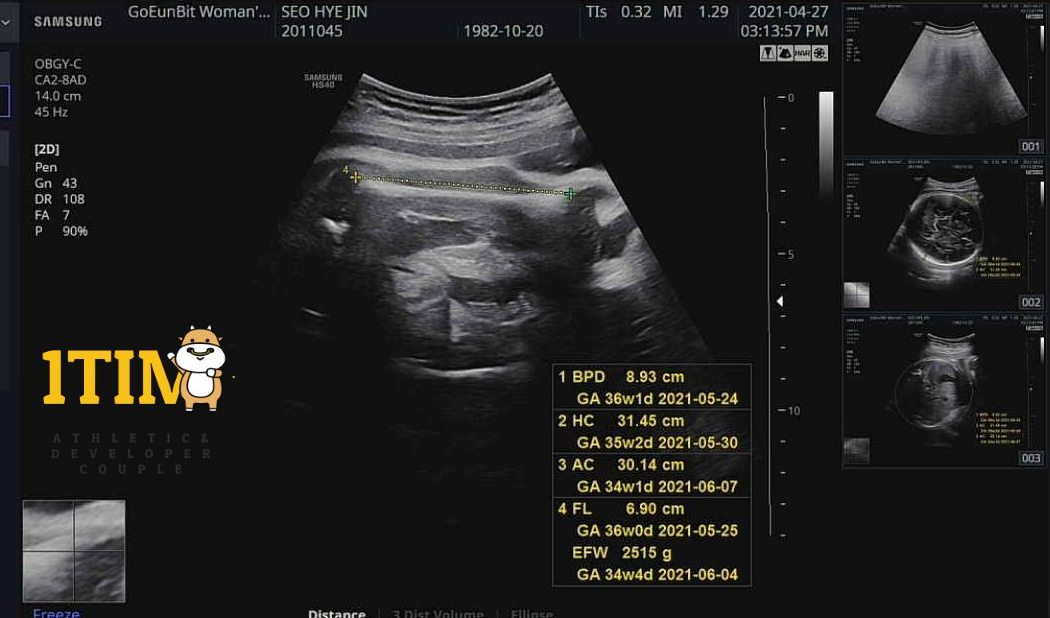

2021. 04. 27 (34주 5일)

오늘은 정기검진!

그동안 크롱이가 주수에 비해 보통 2주~4주 정도 큰편이라 걱정했다.

선생님도 이대로 계속 크면 주수 채우기전에 유도를 하든, 제왕을 해야한다고 ㅠㅠ

내가 노산이기 때문에 자연분만을 고집하면 안된다고 하셨다.

그래서 최대한 아이 키우지 말라고 하셨다.

한때는 크롱이 머리가 4주까지도 크다고 했었는데,

다행히 오늘은 1주일 차이만 난다고 했다.

몸무게도 2주정도 빨랐었는데 오늘은 딱 주수에 맞다.

무게 : 2,515g (34w4d)

5월부터는 아무때나 나와도 상관없다고 하셨다.